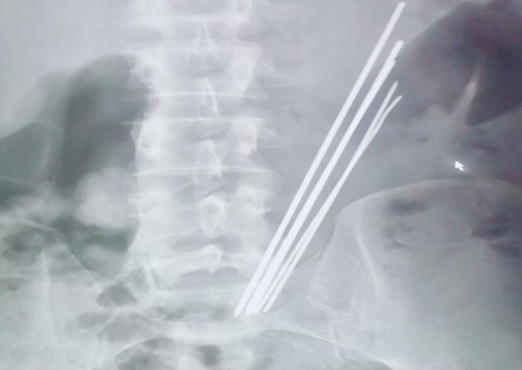

2019年10月30日,延安大學(xué)咸陽(yáng)醫(yī)院內(nèi)鏡中心一如既往,仍是一番忙碌景象。電話響起,我院普外科二病區(qū)來(lái)電,科室就診了一位特殊患者,又一例消化道異物,與此前不同的是,這位病患的異物已吞入達(dá)3年之久,間斷腹痛,未予重視及治療,近來(lái)因臍周疼痛逐日加重,就診于多家醫(yī)院,無(wú)一例外,均建議手術(shù),患者及家屬疲于奔波,最終無(wú)奈接受,遂來(lái)我院要求行手術(shù)治療。主管醫(yī)師接診后積極詢問(wèn)病史,完善相關(guān)檢查,令人訝異的是,3年時(shí)間異物依舊潴留于胃腔之中,腹平片提示為多個(gè)長(zhǎng)條狀金屬異物,棘手之處在于患者拒絕提供關(guān)于異物的詳細(xì)信息。聽(tīng)聞我科上次胃內(nèi)異物取出報(bào)道,主管醫(yī)生抱著試試看的態(tài)度打通了內(nèi)鏡室的電話。

李恒副主任醫(yī)師詳細(xì)了解上述情況后,立即與內(nèi)鏡中心麻醉師張玉河醫(yī)生溝通,暫時(shí)無(wú)法確認(rèn)異物是否嵌頓入胃壁,以及其嵌入深度,普通胃鏡的刺激極有可能加劇患者痛苦,為異物取出造成阻礙,無(wú)痛胃鏡相對(duì)而言,患者痛苦較小,避免了配合度不高等情況,但與此同時(shí),因異物存留于胃腔內(nèi)時(shí)間較長(zhǎng),考慮金屬質(zhì)地,且數(shù)量較多,操作過(guò)程中必然會(huì)面臨很多棘手問(wèn)題,并發(fā)呼吸困難、大出血的風(fēng)險(xiǎn)。消化內(nèi)科一病區(qū)李主任和麻醉醫(yī)師張玉河認(rèn)真翻閱患者相關(guān)信息,制定出嚴(yán)謹(jǐn)、詳盡的治療方案。征得患者及家屬同意后,又一場(chǎng)攻堅(jiān)戰(zhàn)展開(kāi)了......進(jìn)鏡至胃腔,可見(jiàn)5個(gè)長(zhǎng)條形金屬異物滯留,表面光滑,粘液附著,抓取難度非常之大,需在胃腔內(nèi)不斷調(diào)整方向,確保異物以豎直狀態(tài)隨胃鏡緩慢退出,避免異物通過(guò)食管及口腔時(shí)造成的二次損傷,經(jīng)過(guò)反復(fù)不懈努力,最終異物全部安全取出,長(zhǎng)條狀金屬異物最長(zhǎng)達(dá)16cm左右?;颊呒覍匐y掩興奮之情,不停的念叨著“謝謝,謝謝”,內(nèi)鏡下的異物取出讓他們的親人免受手術(shù)之苦,同時(shí)也減輕了經(jīng)濟(jì)負(fù)擔(dān)。